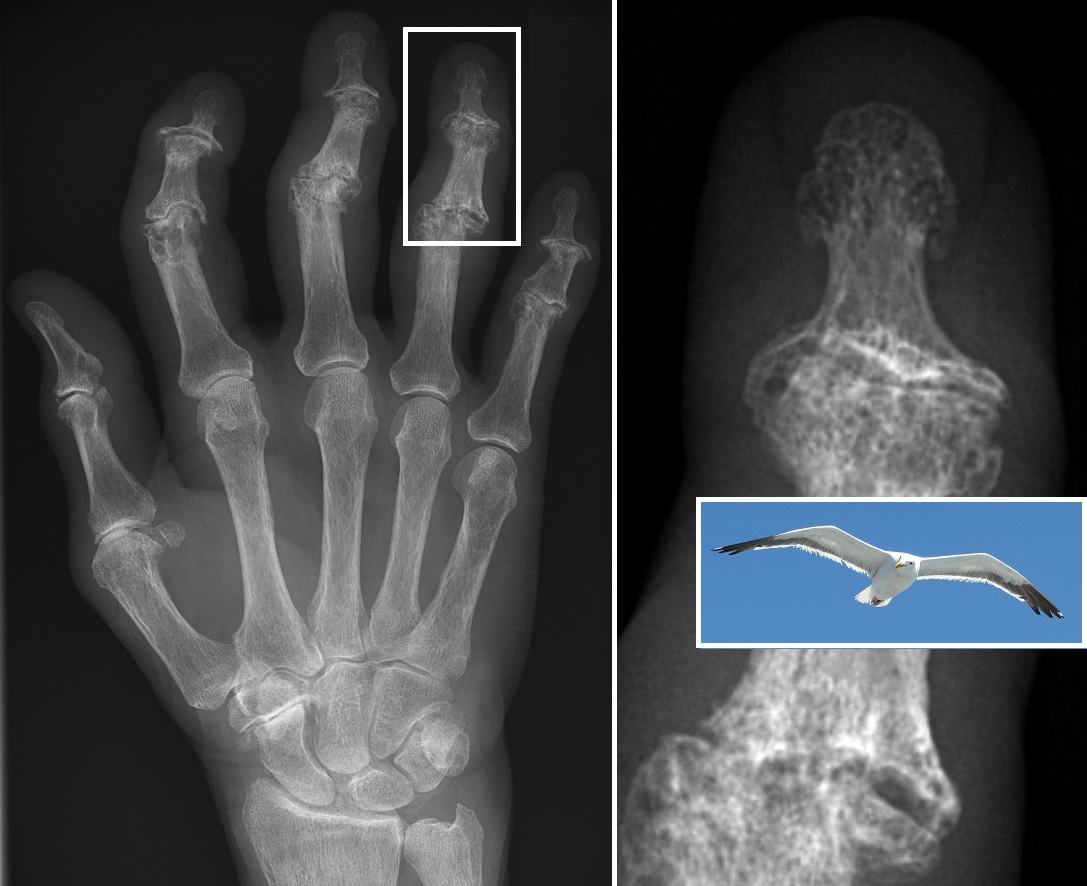

손가락처럼 작은 관절에서는 헤버덴 결절(원위 지절 관절)이나 부샤르 결절(근위 지절 관절)이라고 하는 단단한 뼈 비대가 생길 수 있는데, 통증이 반드시 동반되는 것은 아니지만 손가락 움직임을 상당히 제한한다. 발가락 골관절염은 무지외반증을 일으키는 원인이 될 수 있으며,[15] 발가락이 붉게 부어오르게 한다.

뼈관절염의 진단은 병력 청취 및 신체 검사를 통해 이루어지며, X-ray 촬영으로 확진할 수 있다.[52][53][54] X-ray 소견으로는 관절 간격 협소, 연골하 경화증(관절 주위 뼈 형성 증가), 연골하 낭종 형성, 골극 형성이 나타난다.[54] 다만, 단순 촬영 소견은 신체 검사 소견이나 통증 정도와 일치하지 않을 수 있다.[55]

감별해야 할 질환으로는 류마티스 관절염이 있다. 류마티스 관절염은 손가락 PIP 관절을 침범하는 빈도가 높고, DIP 관절 침범은 드물지만[220], 골관절염은 DIP 관절 침범 빈도가 높다.[220] 또한, 류마티스 관절염은 전신 염증으로 인해 CRP 수치가 상승하지만, 골관절염은 국소 염증으로 인해 CRP 수치가 상승하지 않는다.

일차성 전신성 결절성 골관절염과 미란성 골관절염(EOA, 염증성 골관절염이라고도 함)은 모두 일차성 골관절염의 하위 집합이다. EOA는 드물고 공격적인 형태의 염증성 골관절염으로, 손의 원위 지절 관절에 영향을 미치며 X-ray에서 특징적인 관절 미란 변화를 보인다.[60]